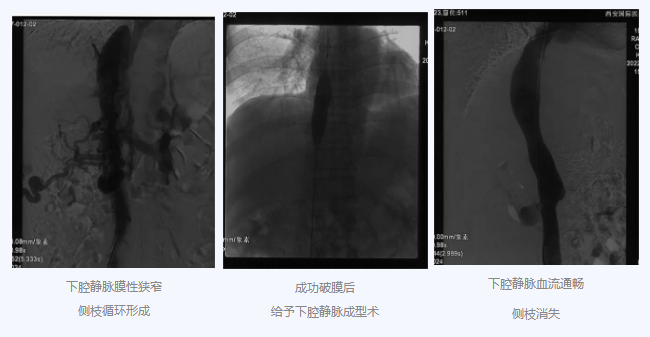

入院后,在韓國宏院長的安排下,臨床經(jīng)驗豐富的醫(yī)師給老謝做了B超、CT 等檢查,結(jié)果顯示:三支肝靜脈近心端閉塞,肝內(nèi)側(cè)枝循環(huán)形成,下腔靜脈近心房入口處隔膜樣狹窄,隨后的DSA血管造影也證實:下腔靜脈狹窄,且有側(cè)枝形成,最終確診困擾老謝20年的疾病為混合型布加綜合征,是一種罕見病。

明確診斷后,韓院長帶領團隊縝密分析老謝的病情,為其制定最佳的治療方案,考慮到老謝的根本病因是下腔靜脈阻塞,介入手術(shù)成為首選治療方法,通過微創(chuàng)介入手術(shù),可準確打通患者的閉塞血管,癥狀迅速緩解。做好充分術(shù)前準備后,為患者行“下腔靜脈成型術(shù)”,精準定位快速貫通,閉塞的下腔靜脈順利開通,手術(shù)圓滿完成。